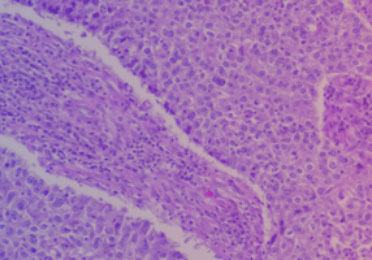

Das DLBCL gehört zu den Blutkrebserkrankungen. Bei ihm vermehren sich reife B-Zellen oder B-Lymphozyten unkontrolliert. Im gesunden Zustand sind diese weißen Blutkörperchen an der Immunabwehr beteiligt. Sie sitzen in den lymphatischen Organen, also Lymphknoten, Milz oder Knochenmark, oder zirkulieren in Blut und Lymphe, um dort Krankheitserreger aufzuspüren. Das erste Anzeichen für eine krebsbedingte Vermehrung ist daher oft, dass ein einzelner Lymphknoten anschwillt. Außerdem verändert sich das Blutbild: Die Zahl an B-Lymphozyten steigt an, während andere Blutzellen, wie rote Blutkörperchen oder Blutplättchen, zunehmend verdrängt werden. Das hat dann spürbare Beschwerden zur Folge.

Neben der Symptomatik, einer körperlichen Untersuchung und dem Blutbild ist für die sichere Diagnose eine Gewebsbiopsie notwendig. Dafür wird meist ein Lymphknoten entnommen.